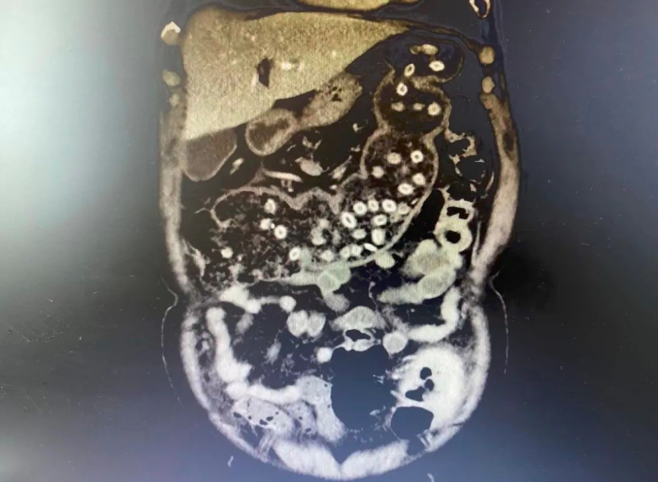

唐爹爹子女联系到长沙市第四医院普通外科(胃肠外科)主任刘杰锋,并将唐爹爹转至该科接受手术治疗。刘杰峰接诊后,给唐爹爹完善CT后“惊呆了”:患者肚子里密密麻麻的杨梅核仿佛连成一串“项链”。由于耽搁已久,情况十分危急,必须马上手术治疗。刘杰峰立刻将唐爹爹送至手术室,为其施行“腹腔镜乙状结肠切除术+腹腔镜下肠造口+内镜下结肠肿块活检术”。